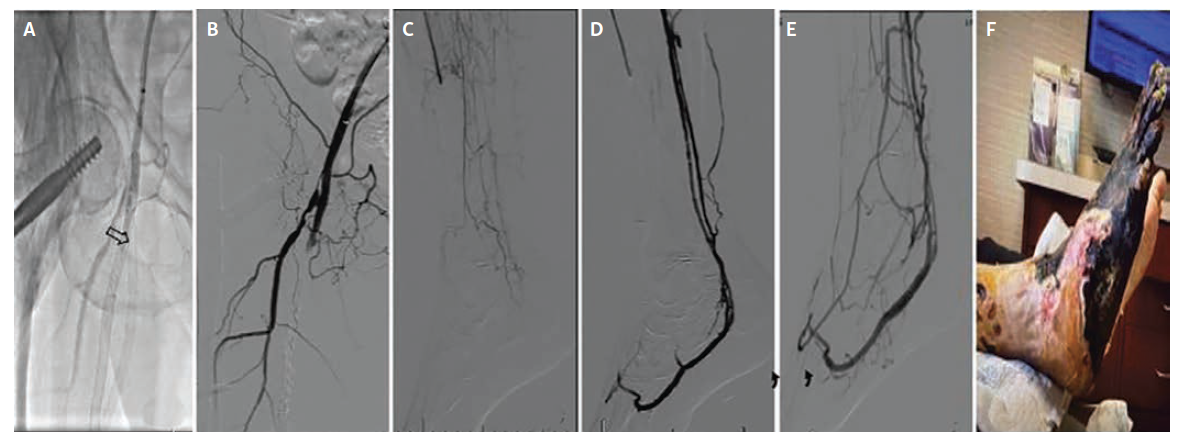

The second patient, a 68-year-old woman (Figure 2), presented with Rutherford class IIa ALI from extensive femoropopliteal and tibial thrombosis, with single-vessel peroneal runoff to the ankle but no perfusion to the foot and occluded ATA and PTA. After an overnight course of catheter-directed thrombolysis, extended with a repositioned infusion, inadequate distal flow remained. Inflow was then optimized with femoropopliteal thrombectomy, angioplasty, and stent relining as well as tibioperoneal trunk angioplasty and peroneal ballooning. Despite these measures, distal runoff remained inadequate, with sluggish peroneal flow and minimal collaterals into the foot. A peroneal-to-posterior tibial vein DVA was then created using a Viabahn 5 mm x 150 mm stent graft across the arteriovenous anastomosis. Completion angiography demonstrated a widely patent, high-flow DVA with brisk opacification of the common/lateral plantar veins and plantar venous arch and strong Doppler signals. Despite these measures, tissue perfusion did not recover and the patient ultimately required an above-knee amputation, which was performed at an outside hospital 3 months after the index procedure; no additional clinical information is available regarding the circumstances leading to this secondary event.